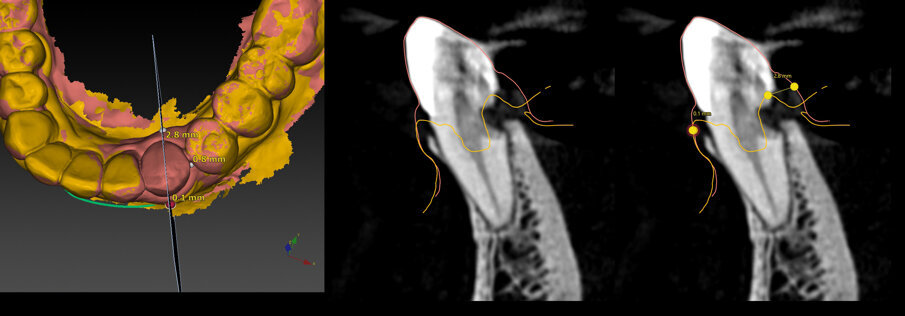

L’esame di primo livello (radiografia endorale) mostra la presenza di un minus dei tessuti calcificati a carico della radice. Si impone per ovvie ragioni un approfondimento volumetrico 3D: soltanto una CBCT ci consentirà di localizzare correttamente la lesione e valutarne la posizione, l’estensione e l’eventuale recuperabilità dell’elemento dentario. Il taglio trasversale della radiografia 3D mostra un riassorbimento radicolare esterno che riguarda la porzione linguale dell’elemento dentario (Figg. 1-4). Il riassorbimento presenta una posizione particolarmente sfavorevole, in quanto si estende già al di sotto del margine osseo crestale su un elemento dentario peraltro già trattato da un punto di vista protesico (Figg. 2, 3). Le opzioni terapeutiche proposte alla paziente sono sostanzialmente due: trattamento endodontico e rifacimento del restauro protesico, previo accesso chirurgico sul lato linguale con allungamento di corona clinica, oppure impianto post-estrattivo con tecnica Socket-Shield. La paziente sceglie questa seconda opzione e firma regolare consenso informato.

La paziente viene sottoposta a scansione intraorale (Trios3, 3Shape) e si procede alla sovrapposizione del file STL con la sequenza di file DICOM ottenuta dalla CBCT (DEXIS OP 3D Pro, Palodex), grazie a un apposito software di progettazione implantare (DTX Studio Clinic e Implant, DEXIS/Nobel Biocare) (Fig. 4) che consente la pianificazione implantare in base al progetto protesico.

Fig. 4_Rx 2d e 3D, con evidenziazione del riassorbimento radicolare, che riguarda l’aspetto linguale e si approfondisce al di sotto del margine della corticale ossea; pianificazione implantare su apposito software di progettazione.